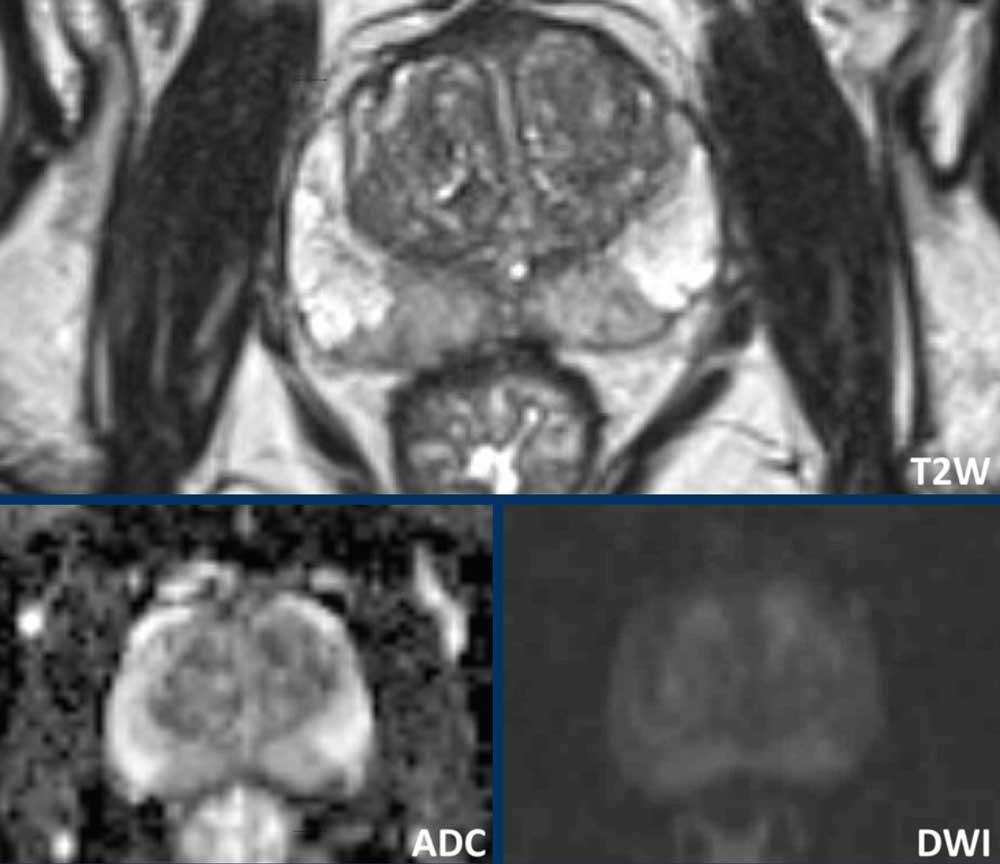

Có một tổn thương ở phần trước bên phải của vùng chuyển tiếp.

Tổn thương có bờ không đều trên chuỗi xung T2W (điểm 4) và giảm tín hiệu khu trú rõ rệt trên ADC (680 mm/s) (điểm 4), kích thước không vượt quá 15 mm.

Tổn thương này tương ứng với PI-RADS mức 4.

Sinh thiết dưới hướng dẫn kết hợp MRI-Siêu âm cho kết quả Gleason 3+4.

Tại vùng ngoại vi bên phải có một vùng giảm tín hiệu nhẹ hình nêm (điểm 2) không có đặc điểm nghi ngờ trên DWI/ADC (điểm 2).

Tổn thương được xếp loại PI-RADS mức 2. Vùng này lành tính và nhiều khả năng tương ứng với teo tuyến hoặc tổn thương viêm khu trú trên mô bệnh học.